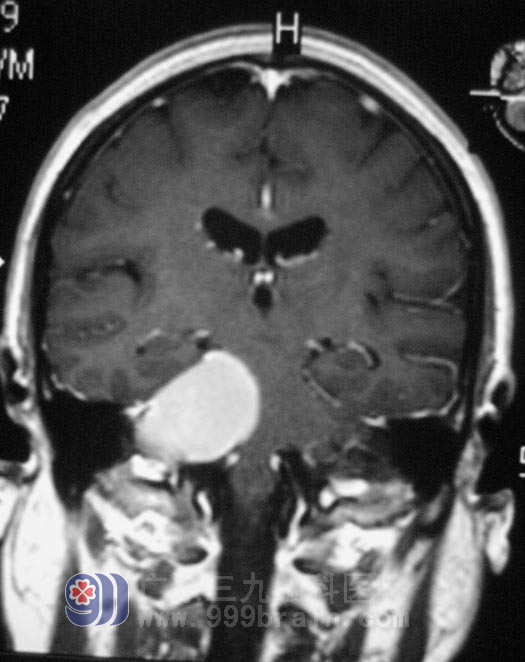

何阿姨的影像资料显示,肿瘤大小约3.0 cm *4.27 cm *3.18cm,初步诊断:1、右侧桥小脑角占位 (考虑脑膜瘤)2、脑积水 3、双侧基底节区腔隙性脑梗塞。完善相关检查后,3月31日,由鲁主任主刀在全麻下给何阿姨行右侧桥小脑角占位切除术+颅内压探头植入术,术中见肿瘤呈粉红色,质软,包膜完整,血供一般,显微镜下利用超声吸引器切除肿瘤,整个手术过程顺利。术后病理结果为:右桥小脑角区)纤维型脑膜瘤WHOI级,经过一段时间的住院治疗,何阿姨右耳的听力、视力、面部感觉都有所恢复,可以自主进食,已经康复出院。

手术前